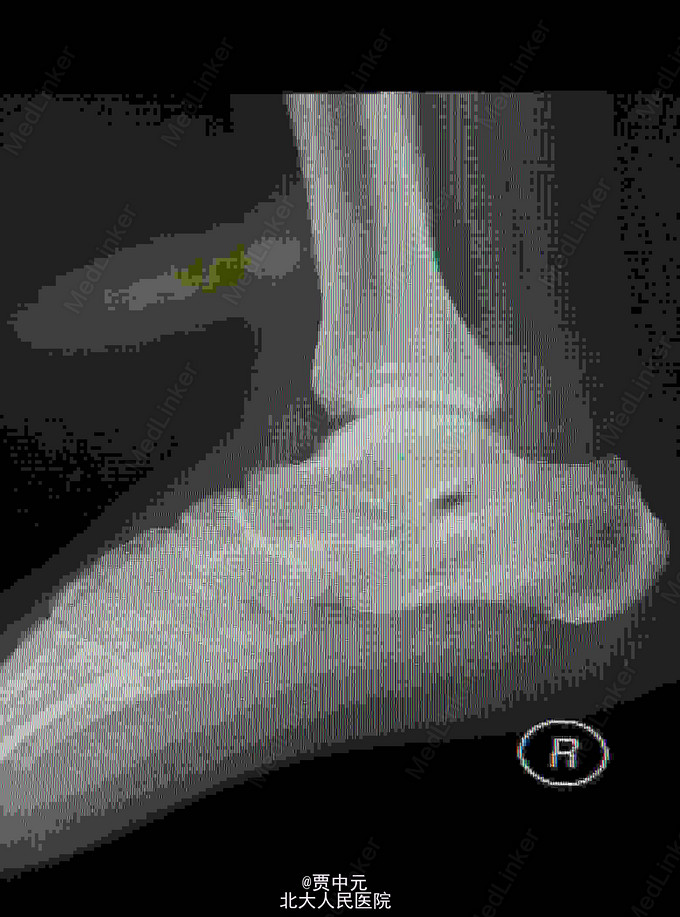

男性,31岁,主因“高处坠落伤致右足跟部疼痛,活动受限1天”于急诊以“右侧跟骨骨折”收入院。 一.病例特点 1.青年男性,高处坠落史。 2.患者约1天前自高处坠落右足着地,当时未昏迷,自觉右足肿痛,不敢活动,在当地医院拍片示:右侧跟骨骨折,为进一步手术治疗收住院。自入院来,患者无发热及胸闷憋气及腹痛症状

入院查体:右足跟部肿胀,局部皮下淤血,压痛,叩击痛,趾端血运可,足趾感觉及活动可,余肢体未见明显异常。 X线:右侧跟骨骨折(外院)

右侧跟骨骨折:高处坠落伤1天,查体:右足跟部肿胀,局部皮下淤血,压痛,叩击痛,趾端血运可,余肢体未见明显异常。 X线:右侧跟骨骨折(外院),根据外伤史,查体及X线检查,故此诊断明确